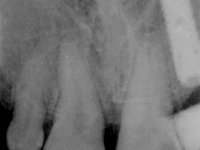

Female patient, 47 years old non-smoker. Tooth 1.3 with endodontic treatment and a cast post and core, rehabilitated with a provisional crown. The two upper lateral incisors are conoid and of small dimension. Tooth 2.2 presents mobility, in agreement with a significant bone reabsorption between teeth 2.1 and 2.3. The two central incisors are separated by a 3 mm diastema and tooth 2.3 presents a crossed occlusion with the opposing tooth. There is also an absence of some posterior teeth and reasonable oral hygiene. In the second intervention performed 8 years later, it was verified that the upper central incisors were chromatically darker and had a longitudinal groove in the enamel which, being pigmented, aesthetically compromised the smile. The work performed in the first phase of the treatment was competent, aesthetically and functionally. Finally, one year after the last intervention, the patient complained of a fracture on the veneer placed on tooth 2.1, probably as a result of being in contact with the abutment of the implant. The rigidity of implant ankylosis may have been the cause of this fracture. I have observed other instances of this type of fracture in identical clinical situations. The veneer of tooth 1.2 was aesthetically compromised and the dental structure itself had small caries and, therefore, its replacement would be recommended.

After clinical and imagological evaluation, the following treatment was proposed to the patient:

• Rehabilitation of the cast post and core with a crown with ceramic-coated Zr infrastructure.

• Orthodontic treatment to close diastema between maxillary central incisor teeth and slow tooth traction 2.2.

• Placement of an implant at the tooth site 2.2. Rehabilitation of the implant with a coronary and gingival component abutment. in which the screw access hole was "camouflaged" with a feldspathic veneer.